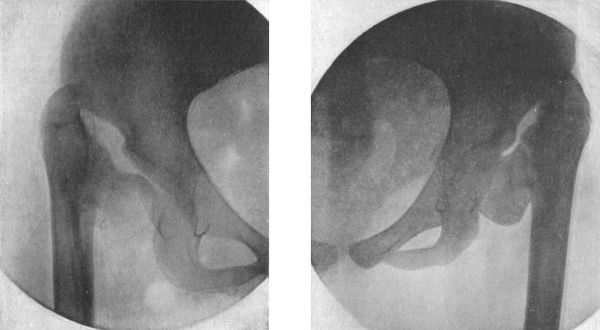

128.Radiogram of Double Congenital Dislocation of Hip in a Girl249

129.Innominate Bone and Upper End of Femur from a case of Congenital Dislocation of Hip250

130.Congenital Dislocation of Left Hip in a Girl251